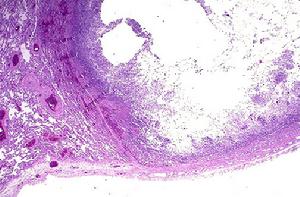

7.胸部X線檢查可呈斑點狀、結節狀或雲絮狀陰影。麴黴球典型的徵象為密度均勻似球狀,其上方有薄壁半月形透亮區,麴黴球可隨體位變動而變動,呈“鐘形陰影”。好發部位為肺上葉.

麴黴球其他輔助檢查:X線上麴黴球表現為肺空洞或胸膜腔內圓形緻密陰影,其邊緣有透光暈影。若空腔較大,尚可見球形陰影有蒂與洞壁相連,形如鐘擺,球形陰影可隨體位變化而改變形態。如果空洞較小,球形病灶填充了大部分空腔,其暈影很小,僅呈一狹長的半月形透亮帶。有學者曾在2例X線平片、體層片和支氣管造影片均無陽性發現的隱源性大咯血患者套用支氣管動脈造影定位後行手術治療,病理髮現1cm左右的細小支氣管囊腫繼發麴黴球。胸部CT檢查特別是高分辨CT的套用為發現細小麴黴球和鑑別診斷提供了有用技術。